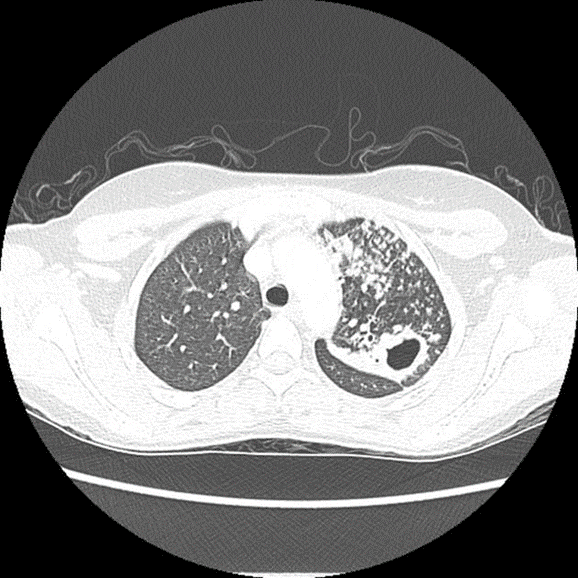

Diffuse nodular infiltration in HIV-TB coinfection in patient with CD4 count less than 200

Individuals with HIV are more prone to be infected with TB, a major cause of death for people with HIV. As HIV impairs the immune system, it is opportunistic for latent TB infection to turn into active TB disease. Without proper treatment, both HIV and TB can significantly shorten lifespan.

Unlike other HIV-associated opportunistic infections, tuberculosis may occur at relatively high levels of CD4 counts. However, its frequency markedly increases in patients with more severe immunosuppression. HIV-TB cases have been observed to have severe immunosuppression at presentation, with several studies reporting CD4 counts of less than 200.

In patients with mild immunosuppression, chest X-ray typically shows upper lobe or bilateral infiltrates, cavitation, pulmonary fibrosis, and shrinkage. The clinical picture often resembles post-primary pulmonary tuberculosis, and the sputum smear is usually positive.